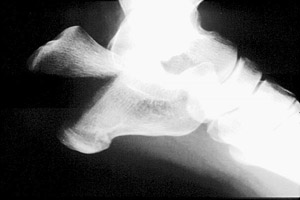

- Click on the image for a larger versionAHarris radiograph. There is a comminuted fracture of the calcaneus.